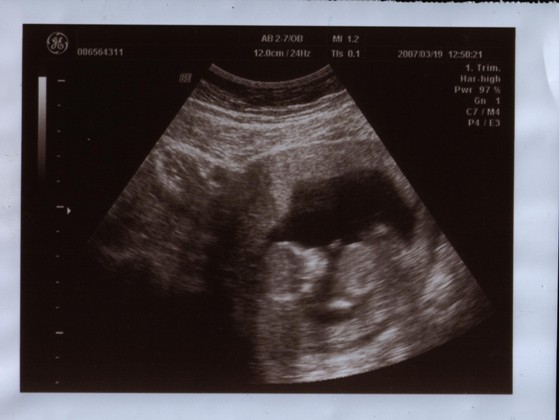

Jövő héten hétfőn kell a 12. hetes genetikai UH-ra mennem, már alig várom.